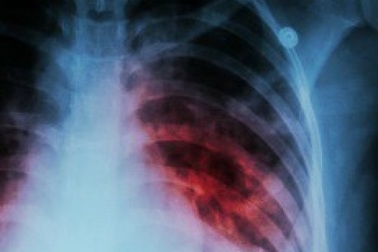

Nguồn lây bệnh lao vẫn tiềm ẩn trong cộng đồngTình hình dịch tễ bệnh lao tại Việt Nam còn rất nặng nề. Theo ước tính của WHO, mỗi năm nước ta có khoảng 182.000 ca mắc lao mới, 9.900 bệnh nhân lao kháng thuốc và khoảng 11.000 người tử vong.

Nguồn lây bệnh lao tiềm ẩn từ hơn 40% bệnh nhân chưa được phát hiệnTình hình dịch tễ bệnh lao tại nước ta còn rất nặng nề, tuy nhiên số bệnh nhân lao được phát hiện, đưa vào điều trị và được báo cáo hàng năm mới chỉ chiếm khoảng 57% số bệnh nhân lao ước tính.

Bệnh lao âm thầm lây lan trong cộng đồngMỗi năm nước ta có hơn 170.000 ca mắc lao mới nhưng mới chỉ phát hiện, đưa vào điều trị, báo cáo hơn 100.000 người. Khoảng 40% bệnh nhân lao trong cộng đồng chưa được phát hiện hoặc báo cáo.